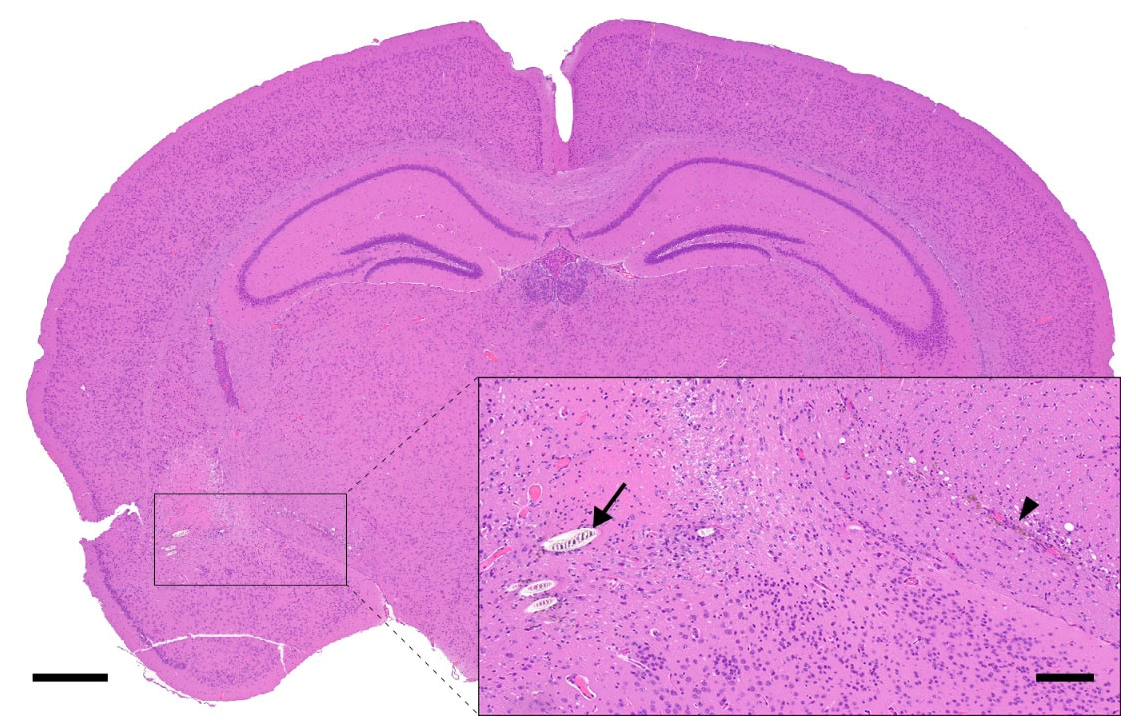

3.2. Lesions Associated with Manual Handling/Restraining

3.3. Blood Collection-Related Findings